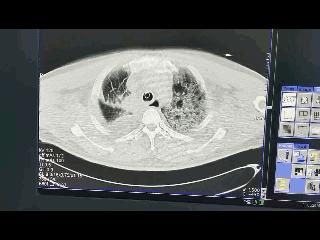

我看了这位朋友提供的CT影像资料了,个人不太明白为何会诊断肺出血。因为提供的资料里面没有关于“出凝血状态”,“手术前后有没有使用一些抗凝的药物”等信息,这些都没有提到。

但是从片子上看,个人认为像一个很严重的感染,就是左肺明显的感染。

因为右上肺切除以后,也就没有了接近20%的肺功能,剩下的是80%左右。如果余下的肺受到感染,当然是呼吸功能不好,维持不了正常的呼吸,需要呼吸机来辅助呼吸。实际上这很可能是感染的问题,而不是出血的问题。